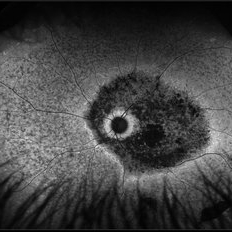

Stargardt's disease

Stargardt's disease

May 2 2013 by Henry J. Kaplan, MD

Typical Bull's eye.

Condition/keywords: bull's eye maculopathy, Stargardt disease